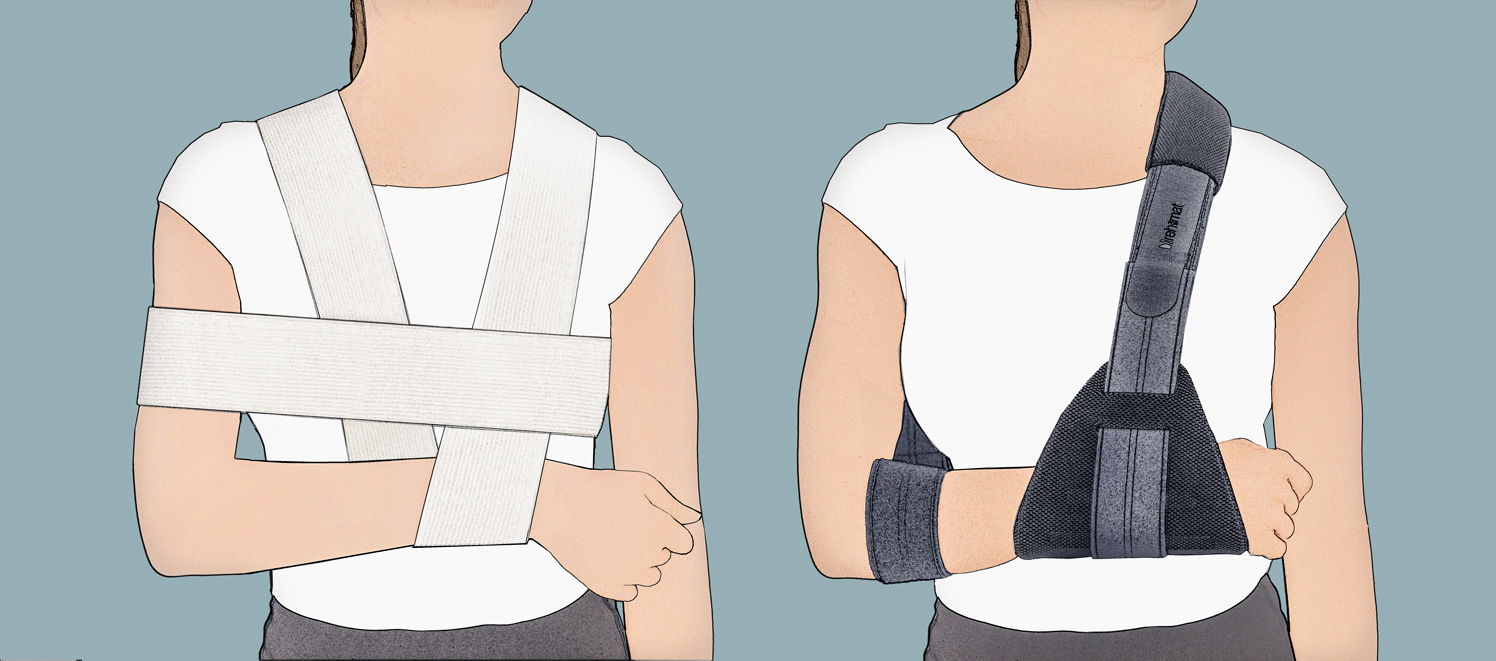

ORTEZA KOŃCZYNY GÓRNEJ Z PODWIESZKĄ TERMOFORMOWANĄ

Orteza kończyny górnej z podwieszką termoformowaną OKG-07 to profesjonalny wyrób medyczny, który unieruchamia i odciąża kończynę górną w przypadku jej dolegliwości bólowych. Orteza składa się z dwóch głównych elementów: termoformowanej podwieszki oraz taśmy obwodowej. Podwieszka nadgarstka została wykonana z lekkiego, termoformowanego surowca Active3D™. Jej kształt pozwala na perfekcyjne dopasowanie do kończyny. Termoformowany materiał to wyjątkowo lekka pianka EVA, niemalże nieodczuwalna dla użytkownika. Konstrukcja podwieszki OKG-07 pozwala na skuteczne odciążenie stawu promieniowo-nadgarstkowego. W odróżnieniu od „podwieszek” wykonanych z tradycyjnego bandaża elastycznego, nasza orteza kończyny górnej OKG-07 zapobiega niekontrolowanemu „opadaniu” ręki, co w rezultacie prowadziłoby do bolesności i zmian zwyrodnieniowych stawu. Termoformowana podwieszka to przyjazna dla skóry gąbka, dlatego nie posiada twardych i ostrych zakończeń. Jej zakończenia są w pełni gładkie, dzięki czemu nie występuje ryzyko otarć skóry użytkownika.

Taśma obowodwa ortezy kończyny górnej OKG-07 to lekki, przyjazny dla skóry materiał SoftComfort™.

Taśma ortezy kończyny górnej OKG-07 posiada szeroki zakres regulacji długości za pomocą zapięcia rzepowego Velcro, dlatego pozwala na ustawienie stawu łokciowego pod kątem 90 lub 45 stopni, w zależności od potrzeb terapeutycznych użytkownika.

Taśma podwieszki kończyny górnej OKG-07 posiada poduszkę odciążającą w rejonie karku, która zapobiega otarciom skóry i zwiększa komfort użytkowania ortezy.

Orteza kończyny górnej z podwieszką termoformowaną OKG-07 zapewnia doskonałe unieruchomienie kończyny górnej w przypadku jej dolegliwości bólowych. Utrzymuje dłoń w pozycji neutralnej, poprawiającej krążenie krwi i limfy w stronę serca oraz zmniejszając obrzęk stawów. Otwarta konstrukcja wyrobu pozwala na stałe monitorowanie kondycji skóry użytkownika i redukuje ryzyko wystąpienia groźnych zmian skórnych tj. martwica.

Dzięki swej unikatowej konstrukcji orteza kończyny górnej z podwieszką termoformowaną OKG-07 może być stosowana zarówno na prawe jak i lewe ramię i może być również z powodzeniem używana wspólnie z innymi ortezami kończyny górnej, jako ich wyposażnie dodatkowe.

Produkt występuje w dwóch wersjach kolorystycznych: czarnej i szarej.